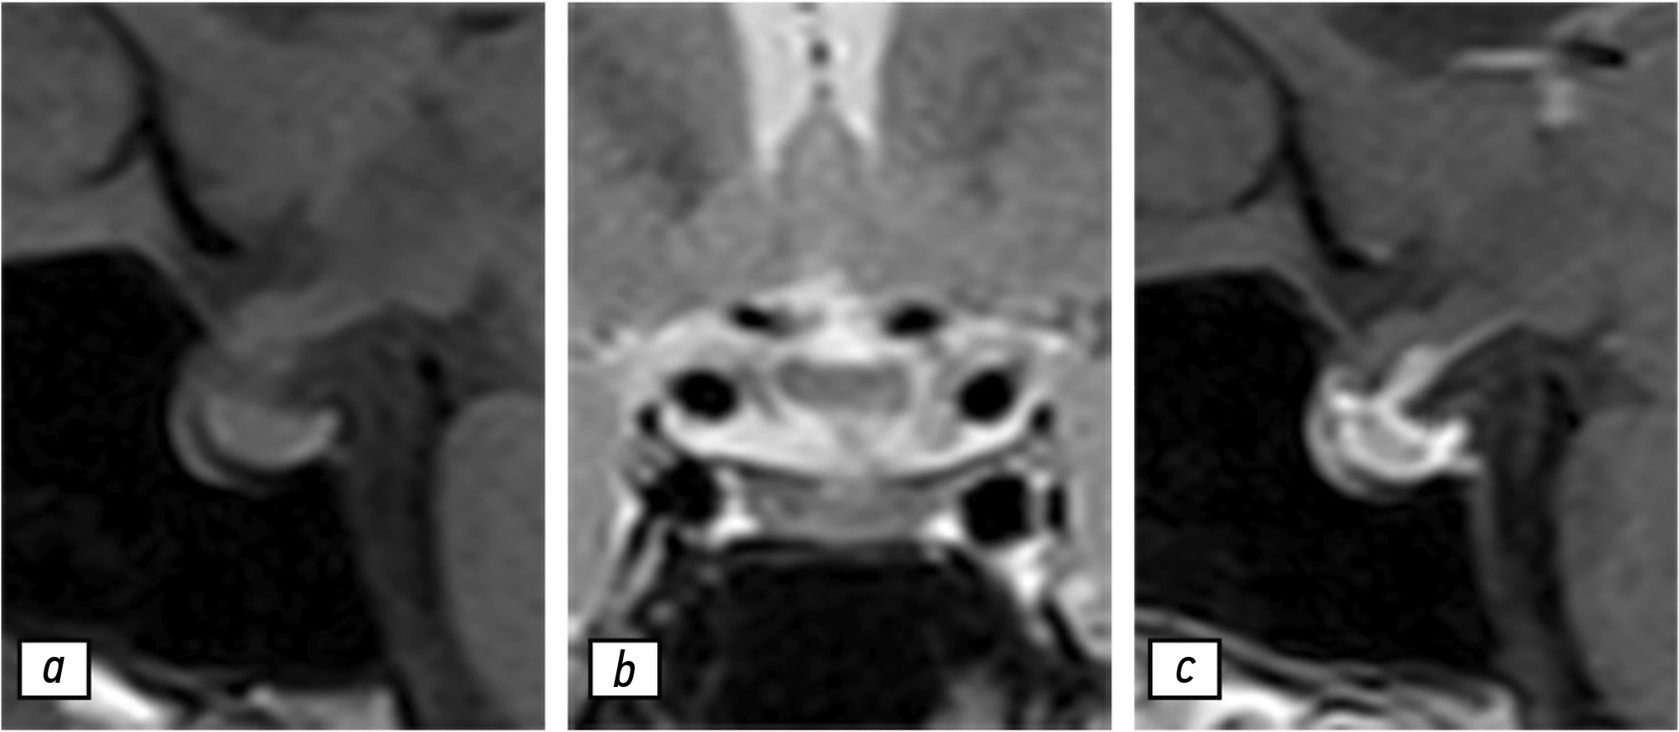

Согласно данным МРТ гипофиза с контрастированием (рис. 1), гипофиз имел слегка гетерогенную структуру и нормальные размеры:

- в сагиттальной плоскости — 1,3 см;

- в вертикальной плоскости — 1 см;

- во фронтальной плоскости — 2 см.

Рис. 1. Результаты магнитно-резонансной томографии гипофиза, 02.05.2020: a — T1-взвешенное изображение в сагиттальной проекции; b — T2-взвешенное изображение в коронарной проекции; с — T1-взвешенное изображение в сагиттальной проекции с контрастированием. Гипофиз (звёздочка) не увеличен и имеет слегка гетерогенную структуру.

Отмечено незначительное отклонение ножки гипофиза влево. После введения гадолиний-содержащего контрастного вещества в центре вещества гипофиза обнаружено незначительное неравномерное усиление магнитно-резонансного сигнала. Несмотря на то что клиникорадиологическая картина не демонстрировала наличие гипофизита, рекомендовано проведение контрольной МРТ по причине гетерогенности структуры гипофиза.